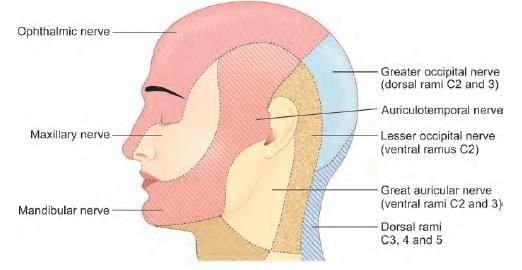

Post parotidectomy, patient feels numb while shaving. Which nerve was involved? (AIIMS May 2019)